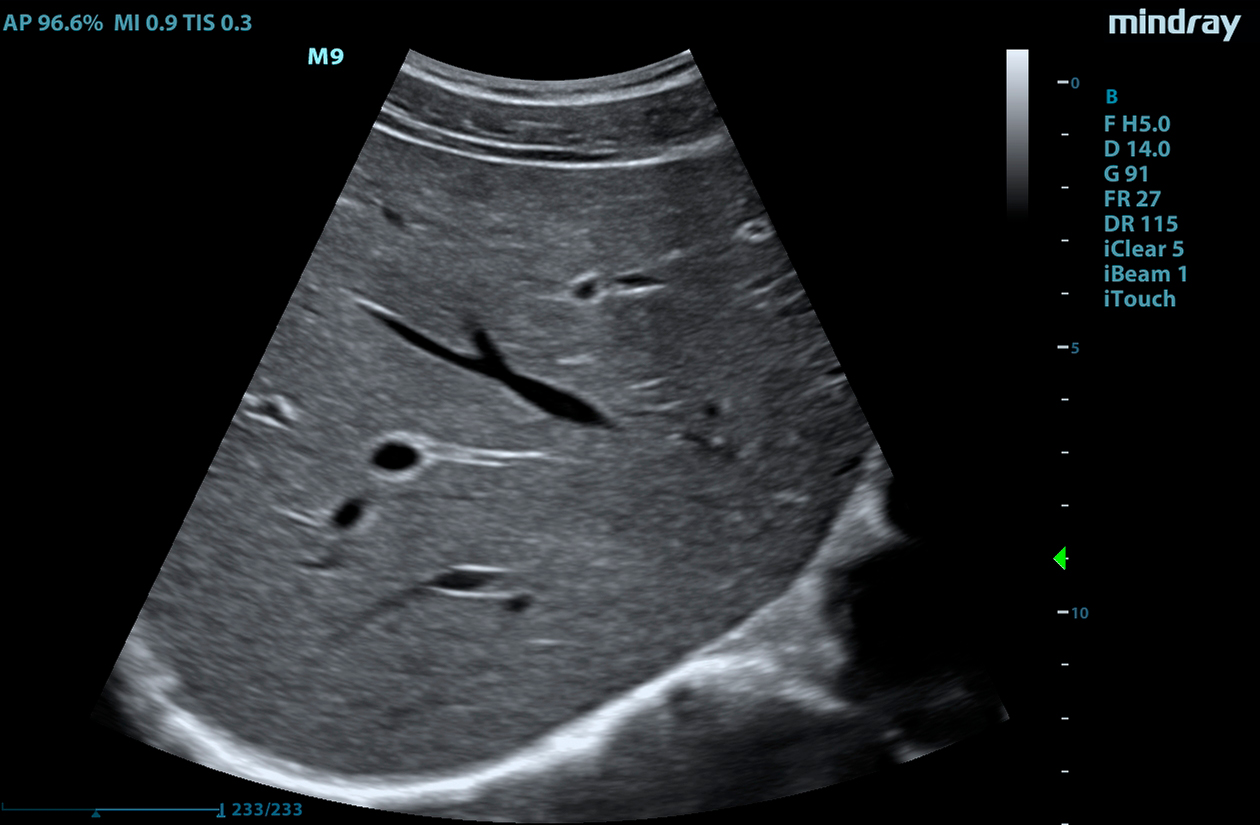

The M9 Ultrasound System Ruby Edition offers a fully-featured, compact ultrasound solution for your most challenging point-of-care exams. Delivering image clarity and advanced capabilities previously only available on larger, cart-based systems, the M9 System defines the new standard for intelligent performance in a mobile, laptop design.

Equipped with single crystal transducers and 3T™ technology for a wide range of exams, the M9 System is a versatile platform for advanced imaging in the vascular lab, emergency departments, critical care environments, and anesthesia practices. The System’s slim profile and ergonomic design allow for effortless flexibility and mobility. Whether it be ultrasound guided procedures at the patient’s bedside or transesophageal echocardiography (TEE) imaging in the critical care unit, this platform can do it all.